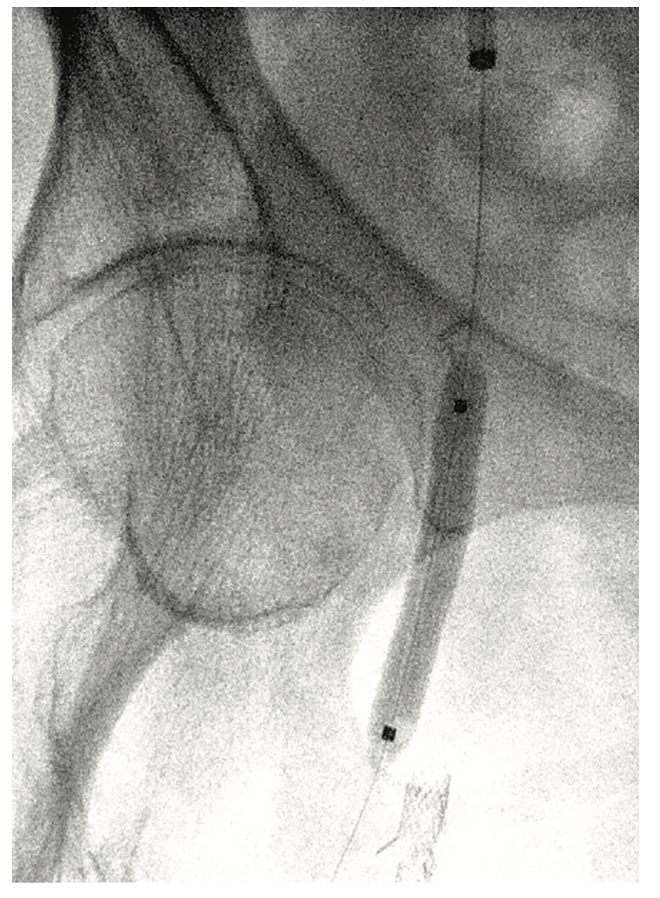

To execute this strategy, a 7 French, 45 cm sheath was placed over the aortic bifurcation and positioned in the very proximal common femoral artery. The patient was anticoagulated with heparin 80 units/kg intravenously. A 6 mm SpiderFX embolic protection device (EPD) (Medtronic) was placed in the largest first-order branch of the PFA and a magnified road map of the lesion was created at 25 degrees right anterior oblique (RAO). A HawkOne LS directional atherectomy device (Medtronic) was selected for its larger plaque excision capability and its shorter nose cone, given the short length of the lesion, and a desire to keep the EPD closer to the lesion and thereby protect more branches (Figure 3). A series of six initial passes with the device at 1-2mm per second was made in a uniform, radial manner. Subsequent angiography demonstrated a marked reduction in stenosis and an additional 5-6 passes were made in a targeted fashion at remaining locations of visible disease. With less than 30% stenosis remaining, an In.Pact DCB (6 mm x 40 mm) (Medtronic) was selected based upon IVUS measurements and inflated to nominal pressure for three minutes (Figures 4-5). Follow-up angiography demonstrated <20% residual stenosis with no evidence of dissection or distal embolization (Figure 6). These findings were confirmed by final IVUS imaging and the procedure was completed without complication (Figure 2B). The arteriotomy was closed by Perclose (Abbott Vascular) and the patient was ambulatory two hours after the procedure. Dual antiplatelet therapy was prescribed for three months following the procedure and low-dose aspirin indefinitely.

the lesion was treated with an In.Pact 6 mm x

40 mm drug-coated balloon (Medtronic).